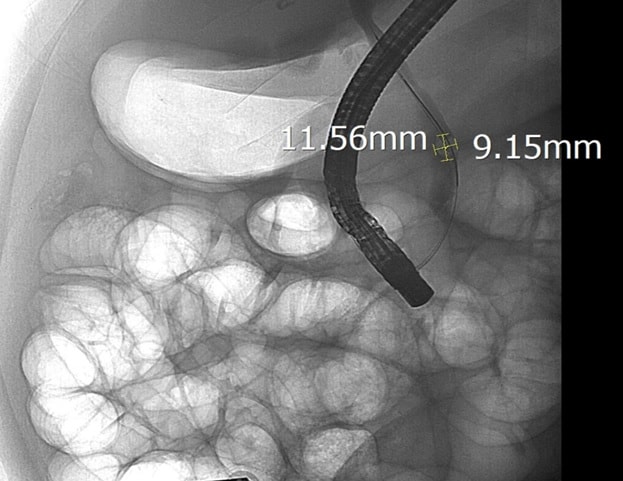

Sau khi hội chẩn, các bác sĩ Khoa Nội Tiêu hóa đã chỉ định nội soi mật tụy ngược dòng (ERCP) dưới hướng dẫn của hệ thống chụp mạch số hóa xóa nền (DSA). Trong quá trình can thiệp, ê-kíp đã lấy thành công viên sỏi kích thước 11,5 x 9 mm, giải phóng tình trạng tắc mật.

Viên sỏi lớn đường mật được các bác sĩ can thiệp thành công.